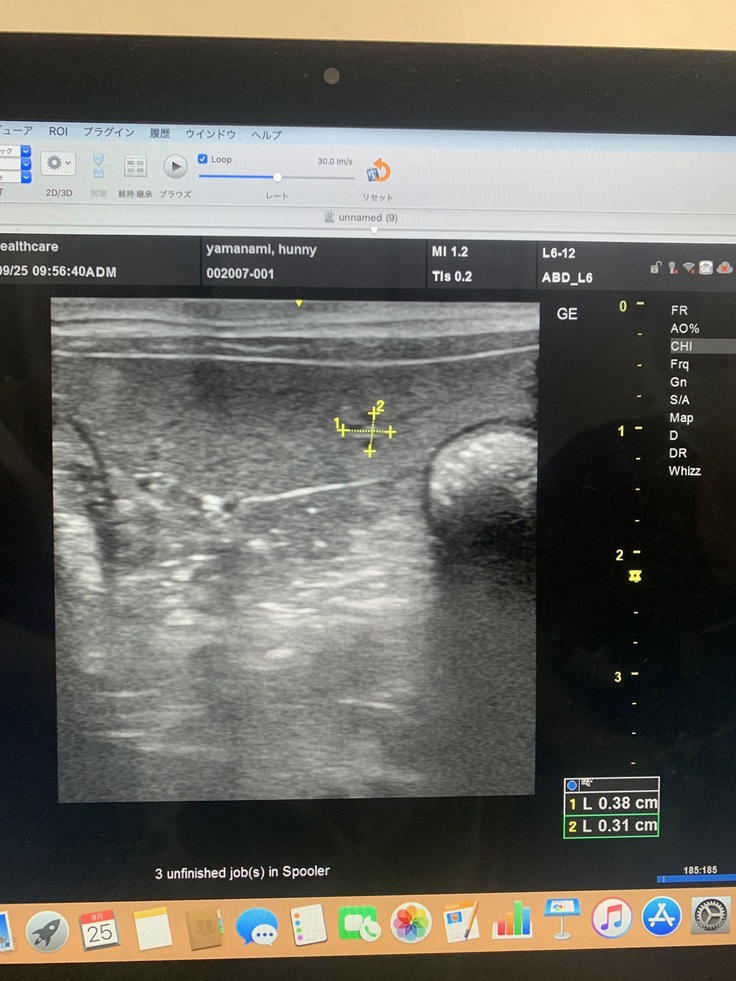

脾臓にしこり、影→1センチ4ヶ所が見つかった